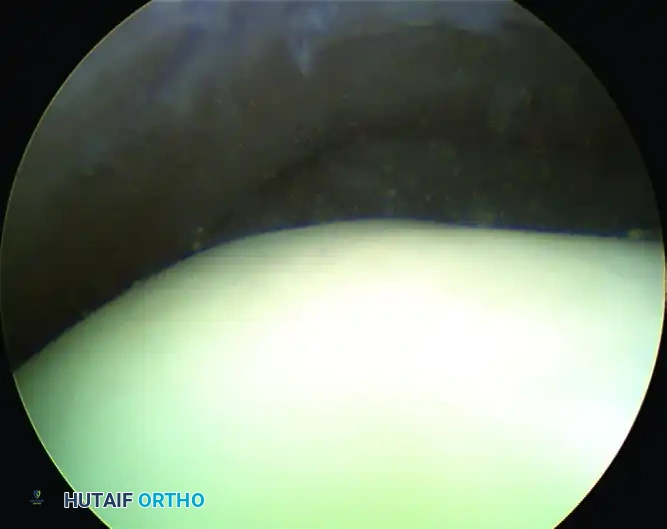

Retrograde drilling of an osteochondral lesion. After confirming intact cartilage, the subchondral lesion is drilled in a retrograde fashion and grafted.

Arthroscopic Debridement and Microfracture

For lesions smaller than 1.5 cm², arthroscopic excision of the fragment, curettage of the necrotic base, and marrow stimulation (microfracture) is the gold standard.

- Preparation: The loose fragment is excised. The sclerotic base of the crater is aggressively curetted until healthy, bleeding punctate bone is encountered.

- Microfracture: An arthroscopic awl is used to create holes 3-4 mm apart and 4-5 mm deep into the subchondral bone to release marrow elements (mesenchymal stem cells) that will form a fibrocartilage repair tissue (Type I cartilage).